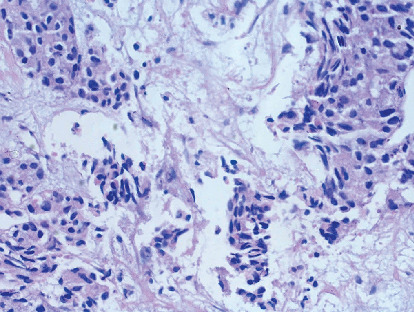

大细胞神经内分泌癌(LCNEC)是一种罕见的侵袭性癌症,主要发生在肺部,但也可以发生在其他器官。它的特点是进展迅速和高转移潜力。我们提出一例晚期LCNEC肺患者表现不佳(PS),需要氧气支持。影像学显示右上叶大肿块,淋巴结病变,伴支气管包膜及侵犯上腔静脉,导致SVC综合征及胸腔积液。活检和免疫组化证实LCNEC。由于患者PS较差,以低剂量单药化疗(卡铂)开始治疗,改善后给予依托泊苷和顺铂治疗。同时给予局部放疗,并调整治疗计划纳入atezolizumab。10个周期后,患者完全缓解,持续6年。该病例强调了老年患者晚期LCNEC管理的复杂性以及多学科方法和免疫治疗的有效性。

Large cell neuroendocrine carcinoma (LCNEC) is a rare, aggressive cancer primarily found in the lungs but can also occur in other organs. It is characterized by rapid progression and high metastatic potential. We present a case of advanced-stage LCNEC lung in a patient with a poor performance status (PS), requiring oxygen support. Imaging revealed a large right upper lobe mass, lymphadenopathy, with bronchial encasement and invasion into the superior vena cava, leading to SVC syndrome and pleural effusion. Biopsy and immunohistochemistry confirmed LCNEC. Due to the patient's poor PS, treatment began with low-dose single-agent chemotherapy (carboplatin), followed by etoposide and cisplatin after improvement. Local radiation was also administered, and the treatment plan was adjusted to include atezolizumab. After 10 cycles, the patient achieved complete remission, sustained for 6 years. This case highlights the complexities of managing advanced LCNEC in a geriatric patient and the effectiveness of a multidisciplinary approach and immunotherapy.